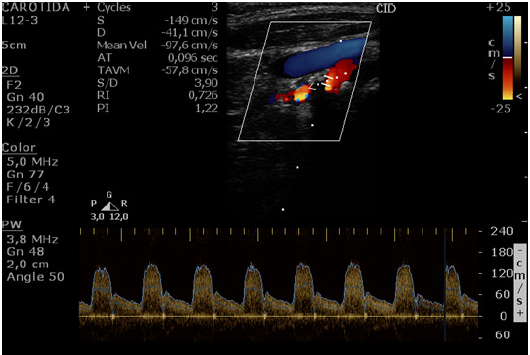

A imagem abaixo refere-se a Doppler de carótida interna

Considerando o Consenso da Sociedade de Radiologia (Society of Radiologist in Ultrasound Consensus Conference - Grant et al., 2003) o diagnóstico mais provável é de